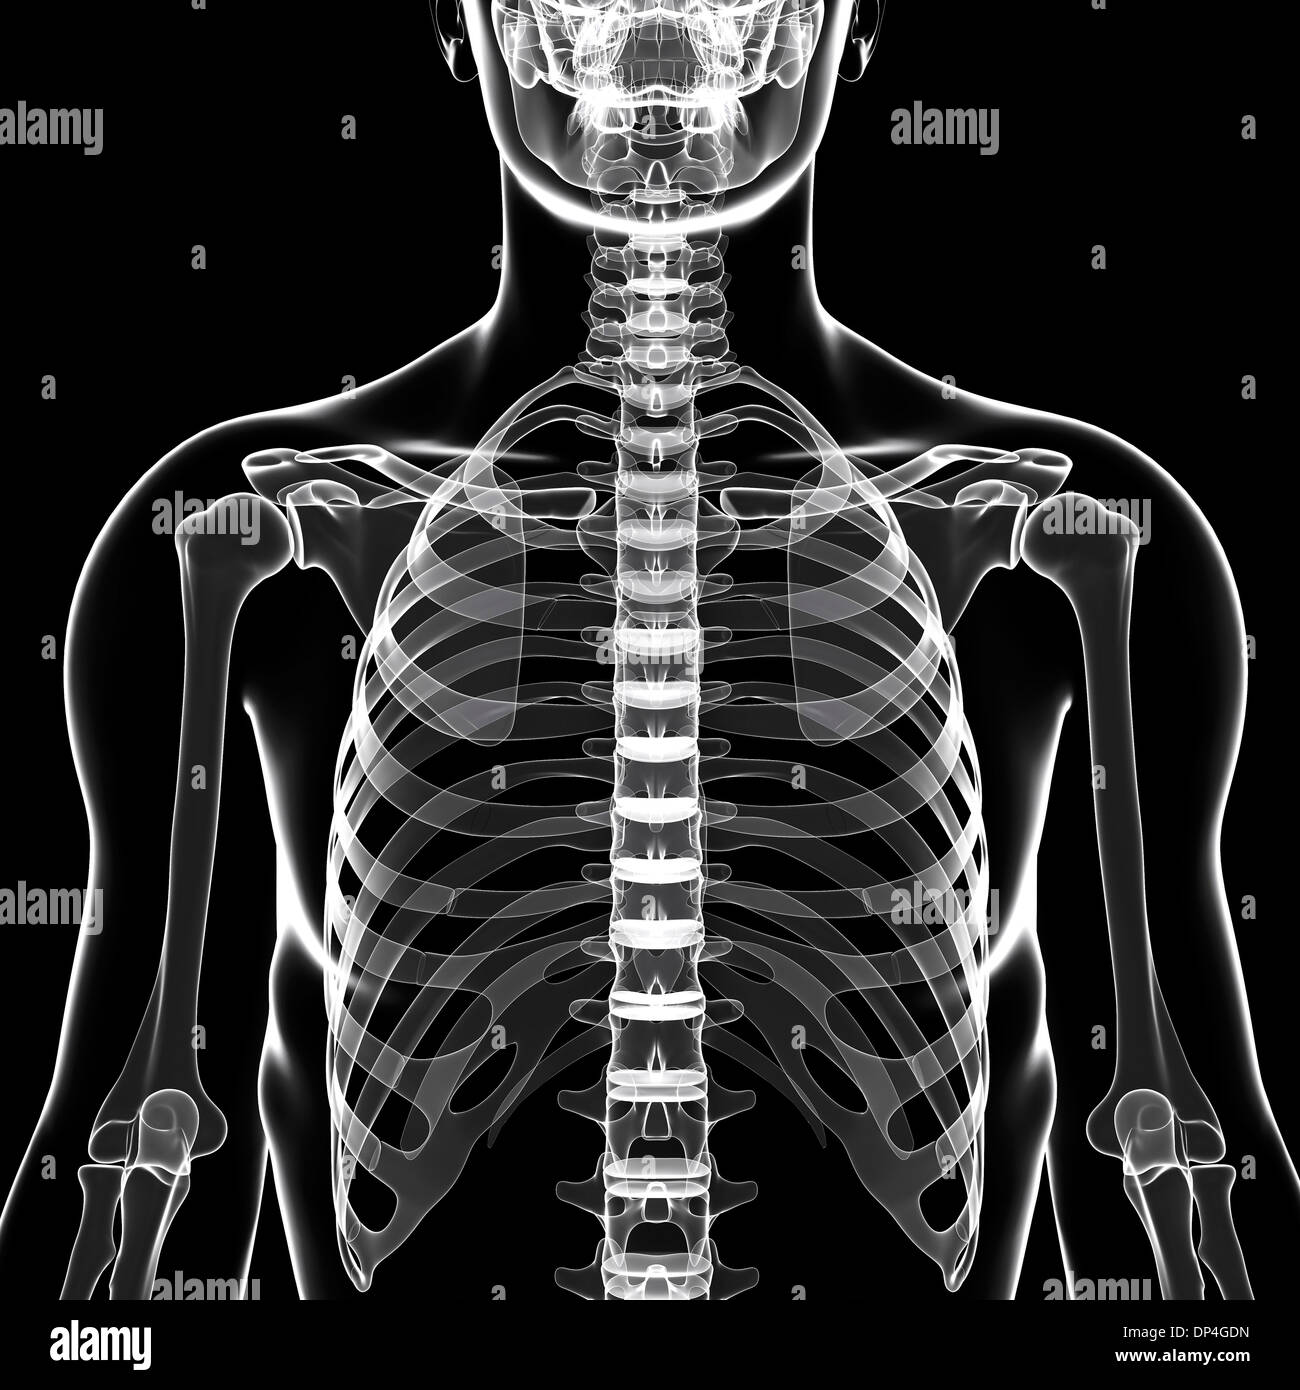

Prepare to be captivated by List, a showcase of real human skull front view black and white imagery powered by ieltschampions.edu.vn. More related visuals are below.

real human skull front view black and white

Posts: real human skull front view black and white